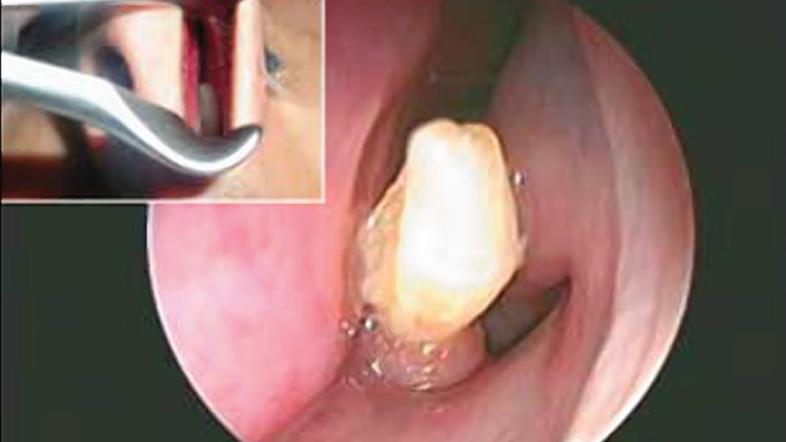

22-letni moški iz Savdske Arabije je imel težave s pogostimi krvavitvami iz nosu, v zadnjih treh letih so se pojavljale najmanj enkrat na mesec. Ko se je le odpravil k zdravniku, je ta ugotovil nenavaden vzrok njegovih težav – v nosni votlini mu je zrasel zob, ki je praskal ob notranjo stran nosu, kar je povzročalo krvavitve.

Študijo primera so objavili v reviji American Journal of Case Reports – John Hellstein, eden od avtorjev študije, je pojasnil, da je sicer tak pojav zelo redek, vendar se ob sekalcih razvijejo dodatni zobje, ki lahko zrastejo tudi navzgor.